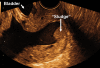

What is amniotic fluid 'sludge'?